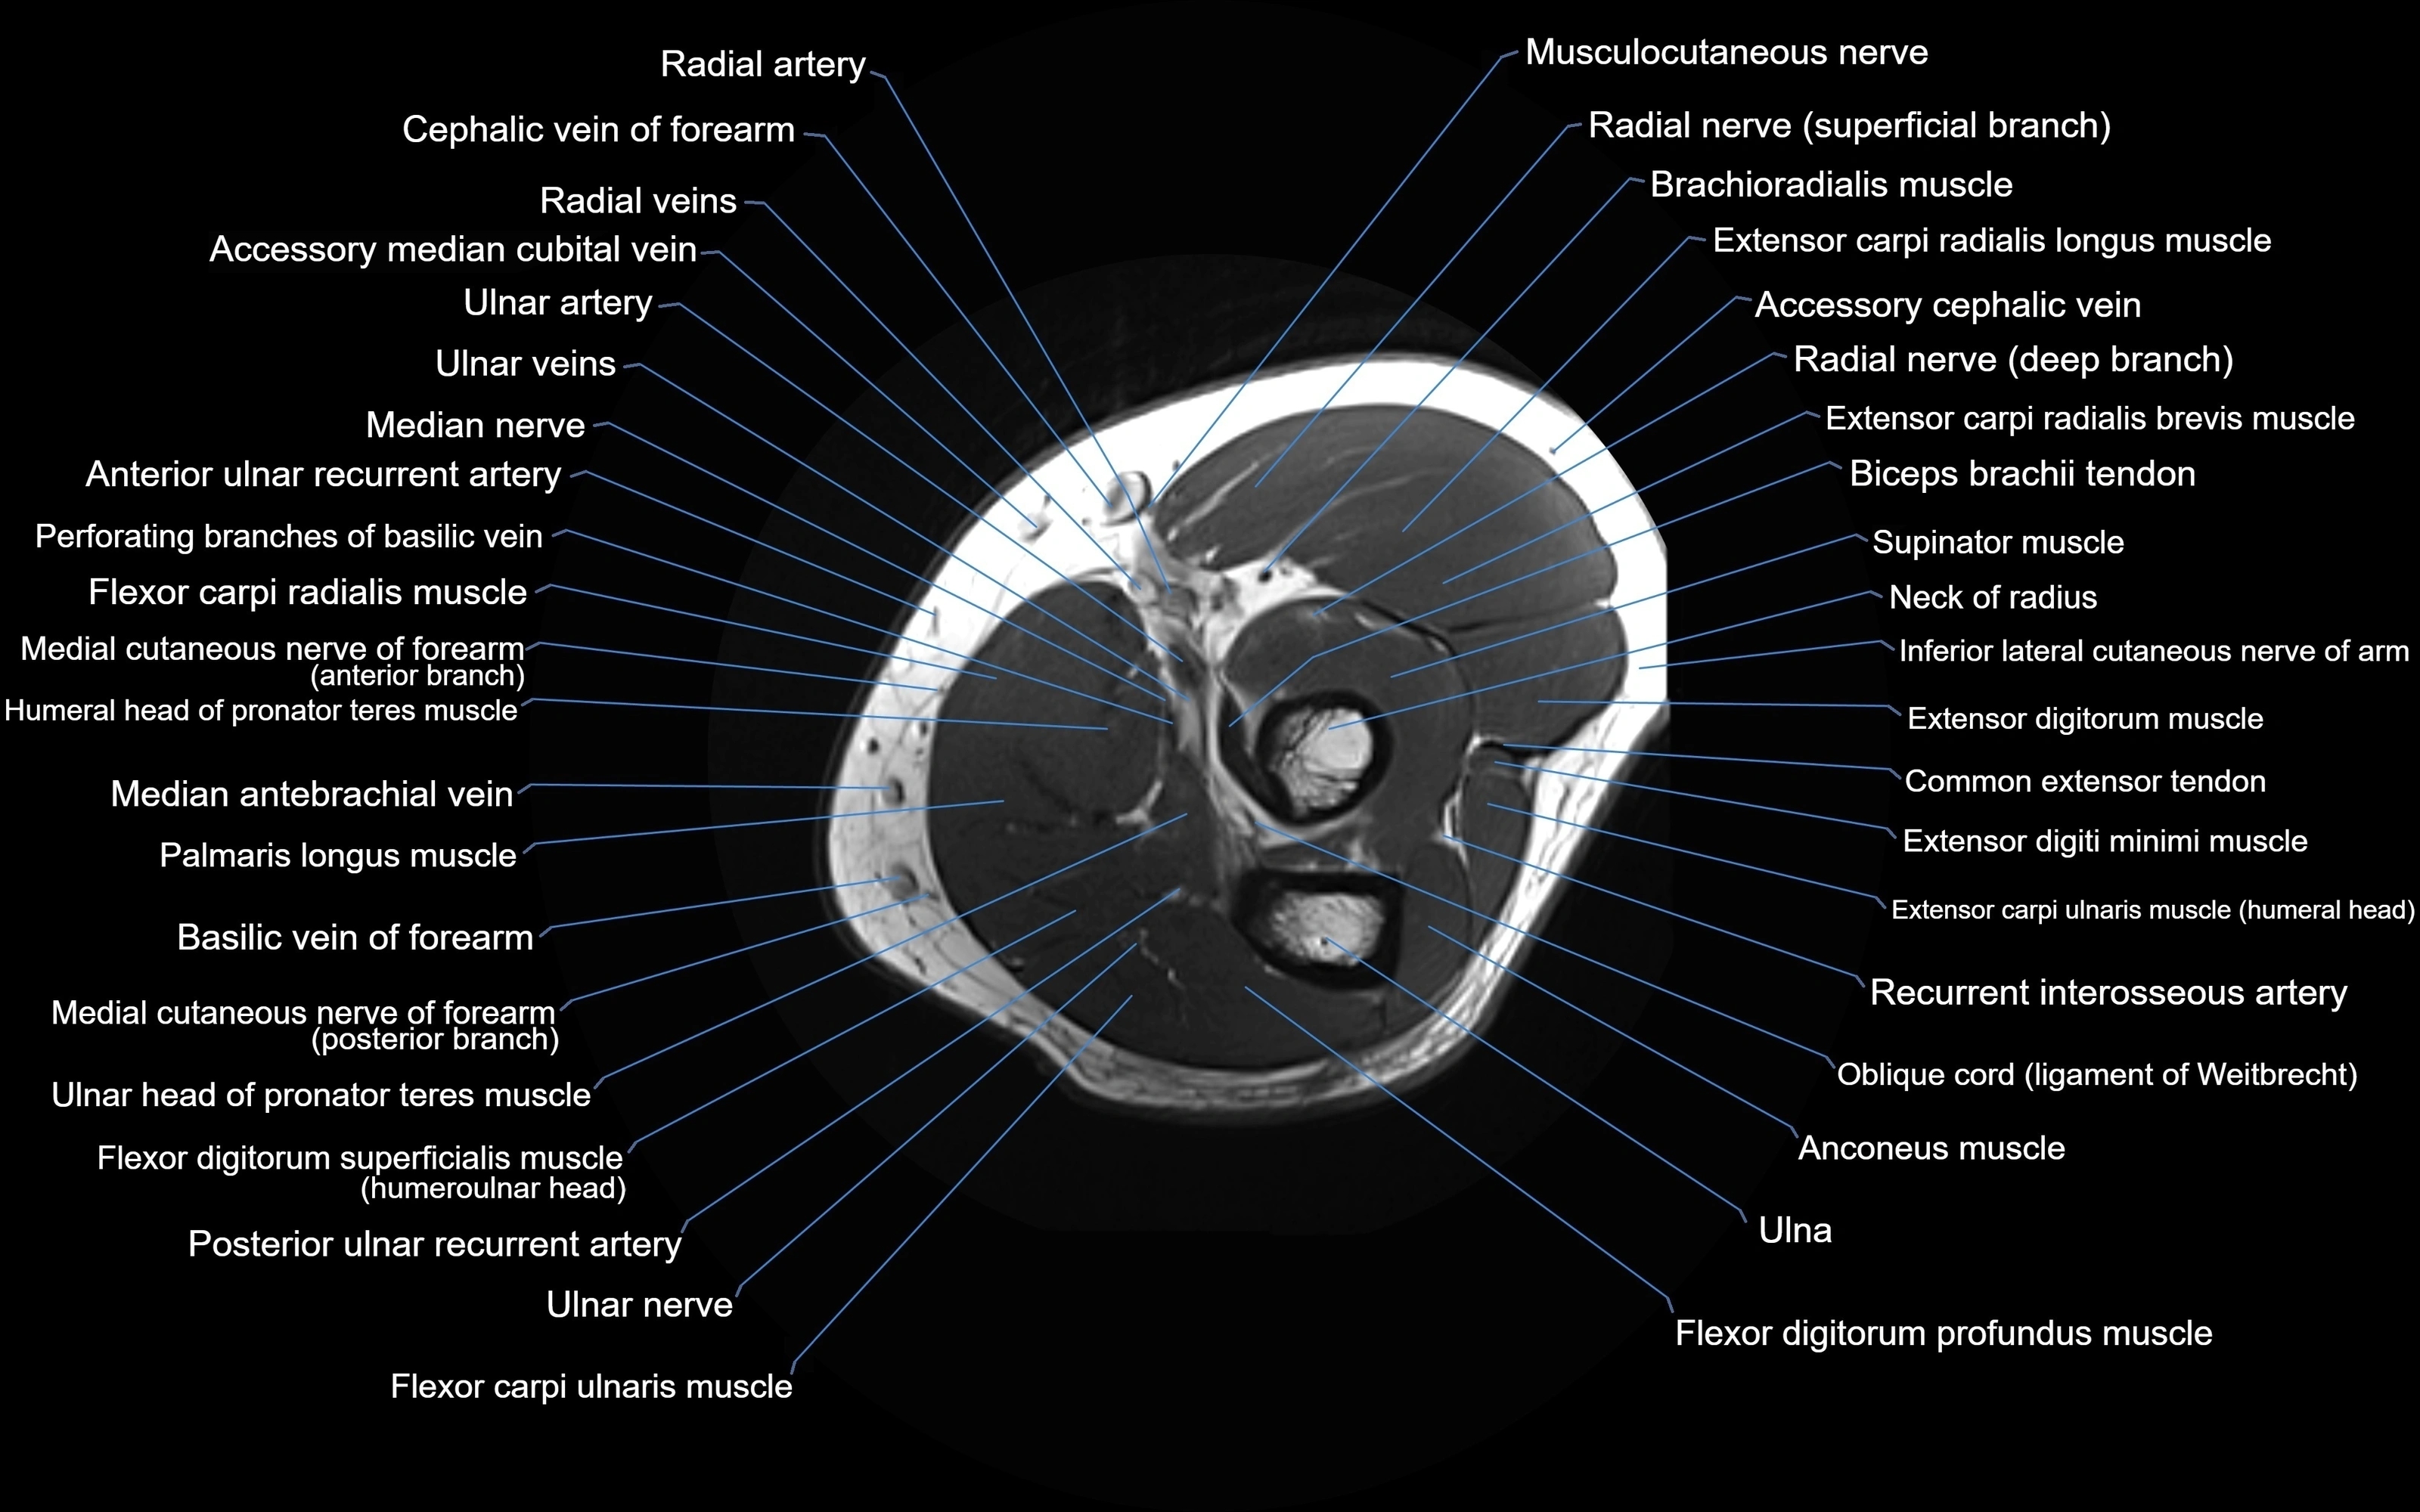

MRI image

image